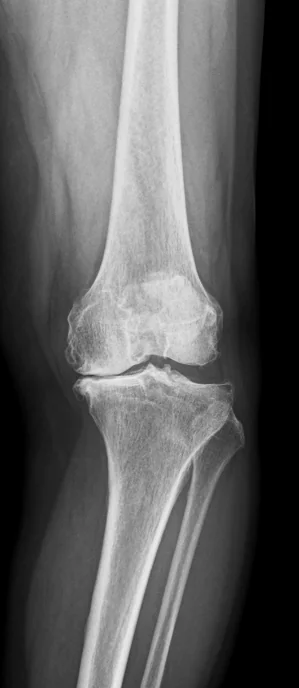

膝の中で何が起こっているか

過剰な体重:

・脛骨大腿骨の圧縮を増加させます 軟骨の変性を加速させます 脂肪組織から炎症性サイトカインを増加させます

・変形性関節症の進行を悪化させます 脂肪は受動的な貯蔵庫ではありません。代謝的に活発です。関節組織をさらに損傷させる炎症性メディエーターを放出します。

つまり、問題は機械的かつ生化学的なものです。